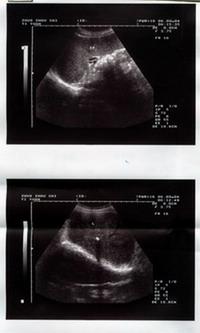

患者:王某 男 58歲 河北省雄縣人 于2004年9月8日中午11時來診。 主治:右肝內膽管結石合并左輸石 主訴:左側少腹疼痛伴腹脹4天 病史:患者于半年前突發左少腹疼痛一次,后癥狀消失;于4天前復出現左少腹脹痛,伴滿腹脹鼓。于涿州市醫院查B超示:1.右肝內膽管結石 2.脾輕大3.胰、膽未見異常 化驗:肝功GPT40單位 現狀:左少腹脹痛,間斷出現右肝區疼痛 叩診:左少腹壓刺痛,右側肝區叩擊痛 治療情況: 本所根據所發癥狀,確定右肝內膽管結石及脾輕大不排除,但主要為左側輸尿管異常,懷疑左輸石存在。即查B超發現:1.右腎輕度積水2.左側輸尿管中下段擴張伴結石 初診治療后即覺左少腹及腹脹減輕。 三診:訴出現尿頻癥狀及尿中可見渾濁。 五診:腹脹基本消失 九診:肝區無叩擊痛,復查B超:肝內膽管結石影像消失。 十四診:無不適癥狀,復查B超未見異常。 以下為檢查報告圖片: